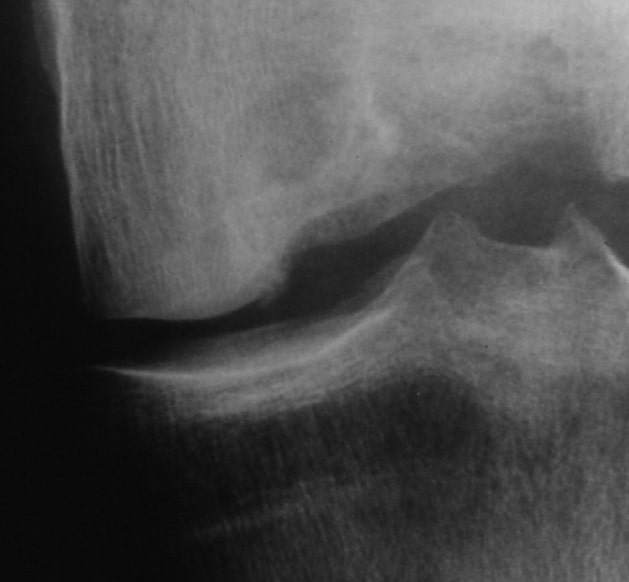

Röntgenbild präoperativ

Tiefer Defekt am medialen Femurkondylus des linken Kniegelenks.